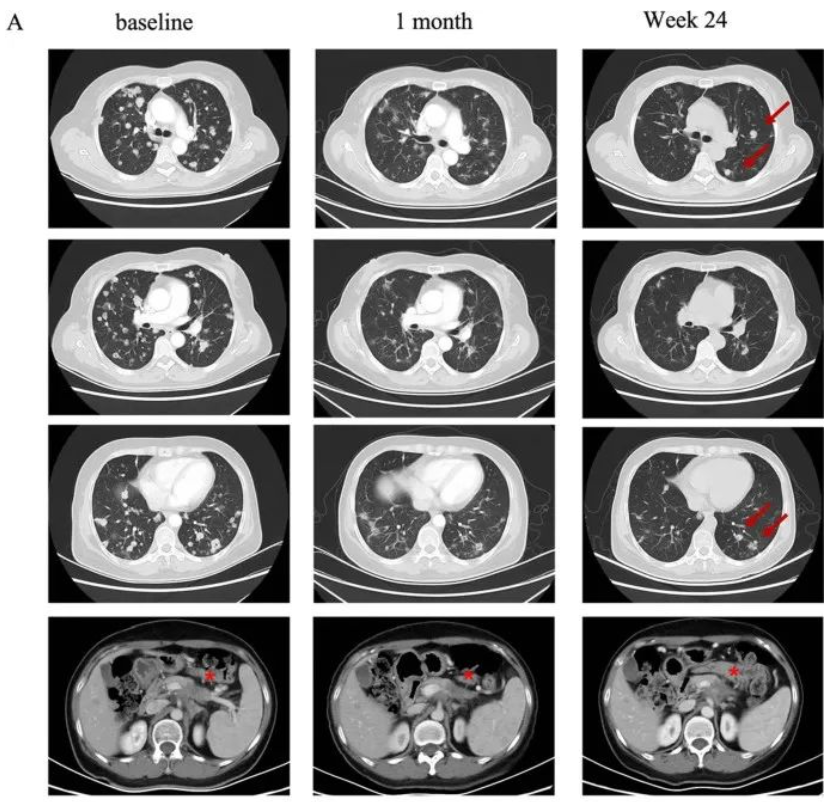

一名58岁的女性胰腺癌患者,伴有肺及淋巴结转移。该患者先后经历一线白蛋白紫杉醇联合吉西他滨和二线伊立替康联合5-氟脲嘧啶治疗后失败。经检测其Claudin18.2表达为2+/70%后入组CT041临床试验。

在进行氟达拉滨、环磷酰胺、白蛋白紫杉醇方案清淋预处理后,患者于2021年9月接受CT041细胞输注。输注后患者出现2级细胞因子释放综合征(CRS),在接受托珠单抗后恢复。根据RECIST v1.1标准,患者肿瘤评估达到部分缓解(PR),肺部转移灶明显缩小。

典型病例2

一名75岁的高龄女性胰腺癌患者,于2019年5月接受了手术切除,诊断为pT2N0期胰腺癌。术后随访5个月时发现肺转移。自2019年12月开始一线S-1单药化疗,在行手术野姑息性放疗期间肺部转移。经检测其Claudin18.2表达为3+/60%后入组CT041临床试验。

在进行氟达拉滨、环磷酰胺、白蛋白紫杉醇方案清淋预处理后,患者于2021年7月输注CT041细胞输注。输注后患者出现2级CRS,经托珠单抗治疗后恢复。患者在CT041输注后第4周进行首次肿评即达到部分缓解(PR),后肺部靶病灶进一步消失达到完全缓解。截至2023年7月末次随访时患者仍处于持续缓解状态。